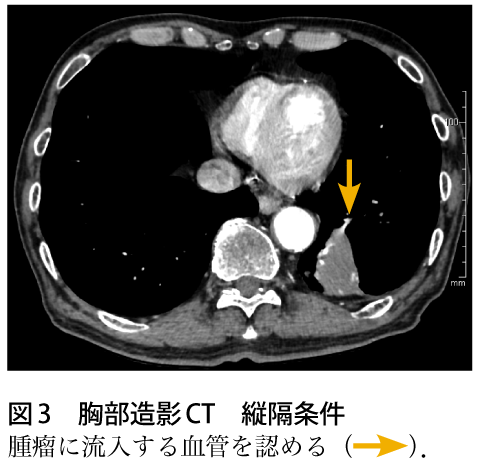

解答 解説 血痰を主訴に来院した70歳代男性 実践 画像診断q A 羊土社 レジデントノート 実践 画像診断q A 羊土社 レジデントノート 羊土社